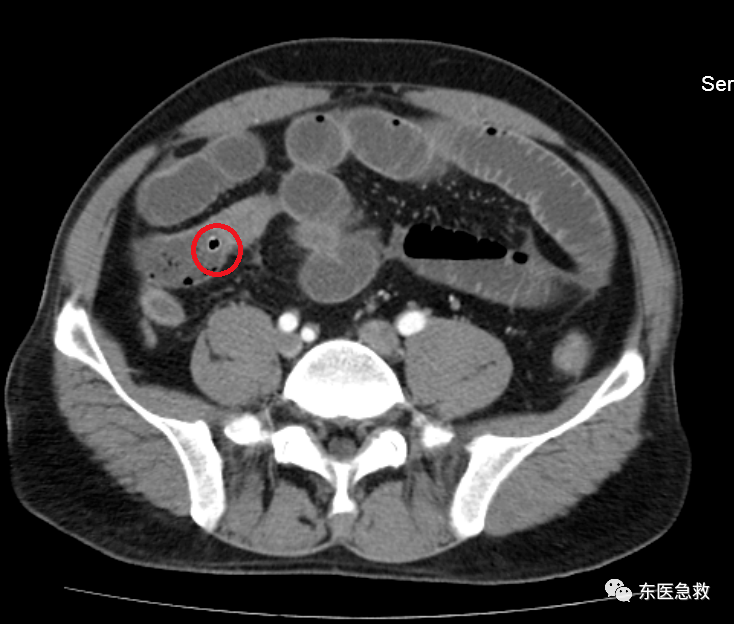

在ct图像上,医生发现了一个一个的小黑点,考虑金叔叔应该是小肠穿孔

图片尺寸734x624